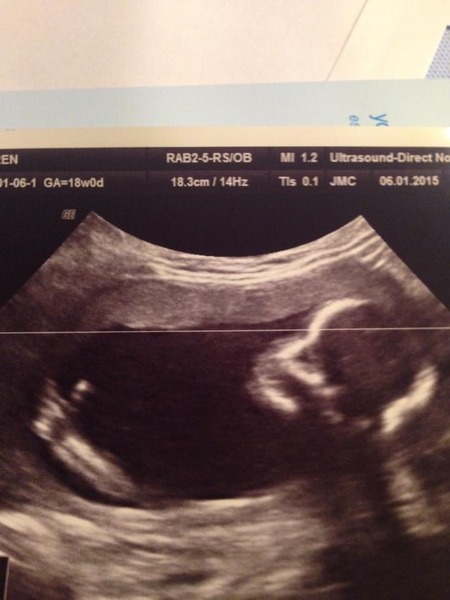

I have posted this pic on facebook but I had a little performer today at the scan doing acrobatics. Bizarrely at the exact moment that I was told that I was team blue, the baby gave a thumbs up!

They dated me at 18+4 so due date 5th June whereas hospital said due date 9th June.

croon that thumbs up pic is awesome!!

What an ace pic croon!